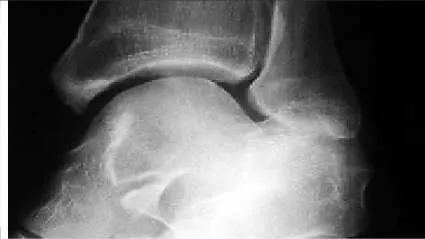

A 14-year-old boy presents for treatment of a painful foot, which has been present for 2 years. He has limited his athletic activities. He has similar symptoms in the opposite foot, although not as severe. On clinical examination, the alignment and appearance of the foot are normal; motion of the foot and ankle is good; and some discomfort is present in the sinus tarsi. Standard radiographs, of which the lateral view is presented, include anteroposterior, lateral, and oblique views. Because the diagnosis is unclear, more imaging studies are required. The next study to obtain is:

Correct Answer: Axial views of the subtalar joint (Harris)

The radiograph demonstrates changes in the subtalar joint suggestive of a middle facet coalition. Note the sclerosis of the joint surface. Although a computed axial tomography scan may be helpful, standard axial views of the subtalar joint (Harris) taken in the plane of the joint are usually diagnostic of tarsal coalition. Motion of the subtalar joint may be normal in the adolescent with a tarsal coalition.